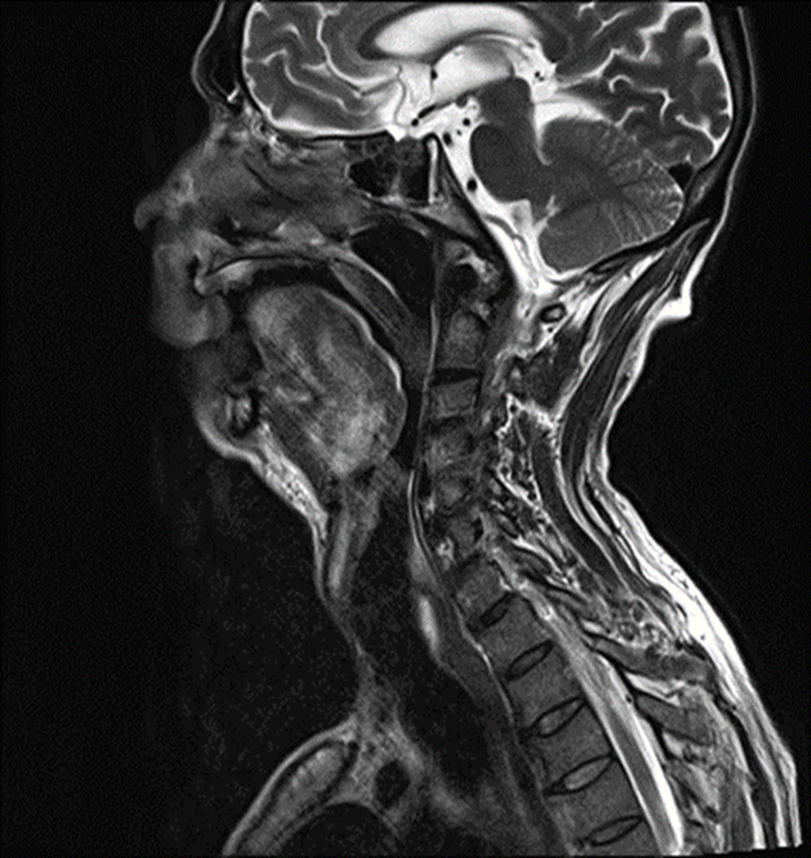

Alternative Method for Airway Approach in Anesthesia of a Newborn with Occipital Encephalocele

Thatiane Noel Ximenes, Marco Antônio Cardoso de Resende, Rogério Luiz da Rocha Videira, Andrea Jorge e Silva, Joana de Almeida Figueiredo, Iara Tânia Gonçalves, Bruno Camara de Resende